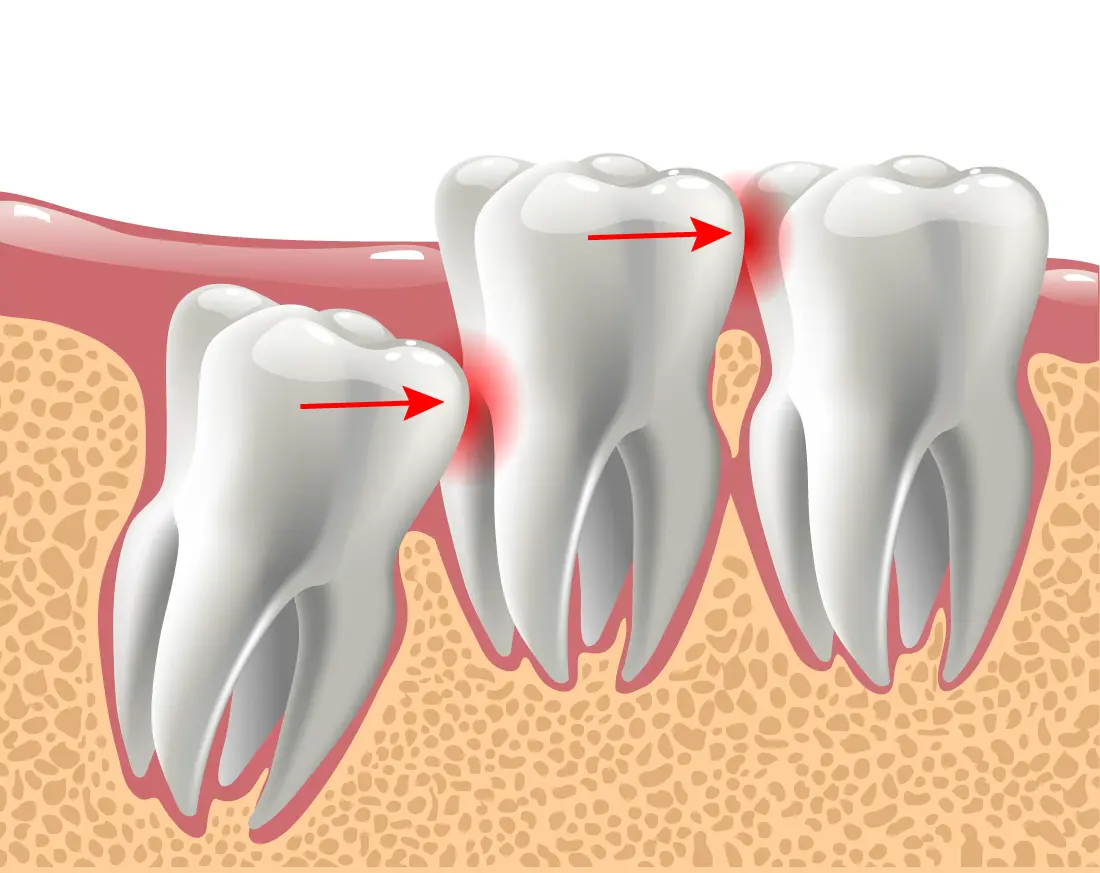

Wisdom teeth often have to be extracted to ensure the rest of your teeth stay healthy. Most wisdom teeth erupt misaligned, which can cause tooth crowding and disruption in your teeth and gums. This is not only painful but can make oral hygiene more difficult. Another common reason for wisdom teeth extraction is a partial eruption. This encourages bacteria to accumulate in the pockets of your gums, putting you at risk for gum disease, infection, and tooth decay. That being said, sometimes wisdom teeth don’t always need to be removed. If your wisdom teeth erupt properly aligned and don’t impact your other teeth, your doctor may not recommend extraction. But generally, wisdom teeth need to be removed to preserve a healthy smile.

Wisdom teeth can cause pain and discomfort. They have no limitations in how they erupt, often growing sideways or putting uncomfortable pressure on your other teeth. Wisdom teeth removal will relieve the pain and release your teeth from the pressure.

Erupting wisdom teeth may put pressure on your surrounding teeth. This often disrupts the alignment of your teeth and can misalign a previously straight smile. Tooth crowding is also problematic in keeping up with a healthy oral hygiene routine.

There are many reasons why wisdom teeth removal may be necessary. This includes wisdom teeth growing in at the wrong angle. They can grow sideways, partially erupt, or even become trapped underneath the gum and bone. Impacted wisdom teeth can take many positions in the bone as they try to find a pathway to successfully erupt. All of these reasons make wisdom teeth removal necessary to preserve your oral health.